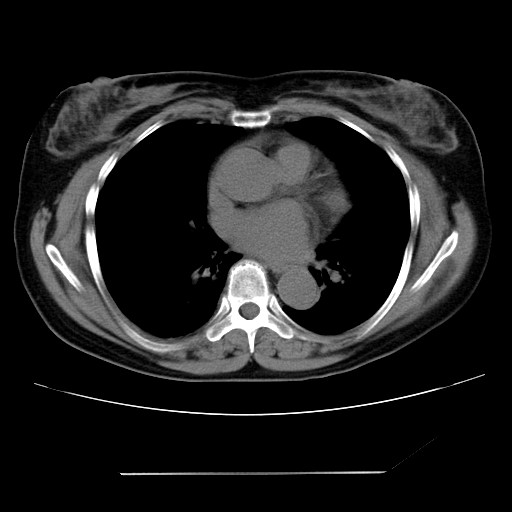

女性,62岁,长期咳嗽,既往从事工作有粉尘接触,有高血压病史,110/150mmhg,近日咳嗽加重,脸面浮肿,请大家帮看下,

1、尘肺;2、慢性支气管炎合并肺部感染;3、心影增大(左房、左室大),考虑高血压性心脏病。

心包有积液吗?

慢支并肺部炎症;右肺结核球?主肺动脉、右肺动脉影不宽,右心室不大,不支持肺心病;无心包积液。